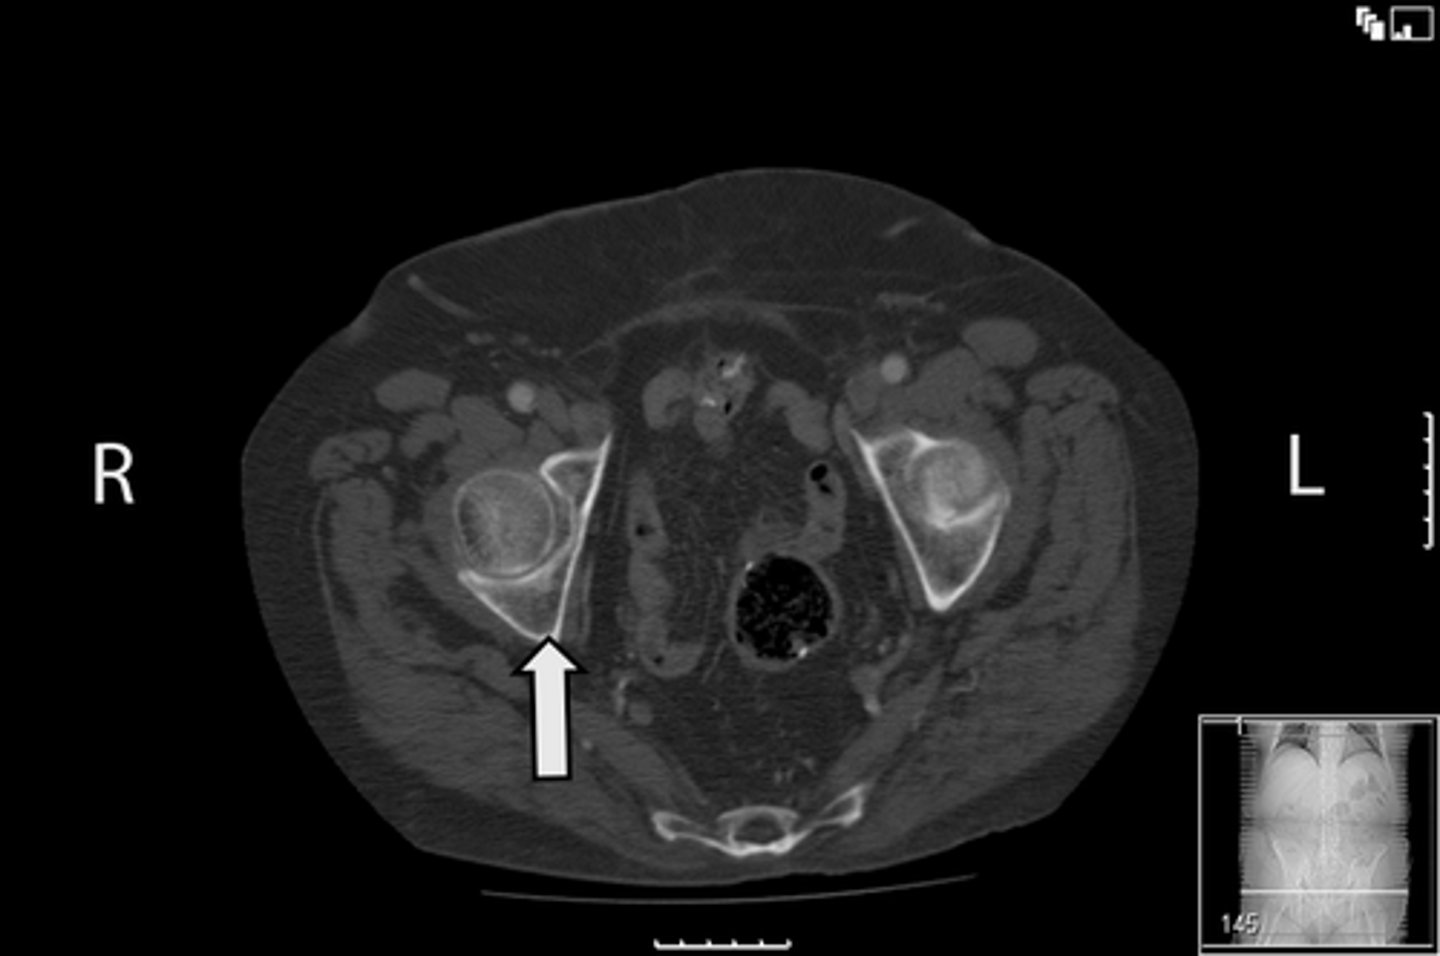

Axial bony pelvis CT

What is the image?

32

L ilium

<p>What is indicated in the image?</p>

New cards

What is indicated in the image?

34

R ilium

36

Sacrum